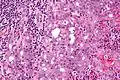

Basophilic, bland cells similar to acinar cells. Growth pattern: solid - acinar cells, microcytic - small cystic spaces mucinous or eosinophilic, papillary-cystic - large cystic lined by epithelium, follicular - similar to thyroid tissue.

These tumors, which resemble serous acinar cells, vary in their behavior from locally aggressive to blatantly malignant.

Intermed. mag. Very high mag.

Very high mag.